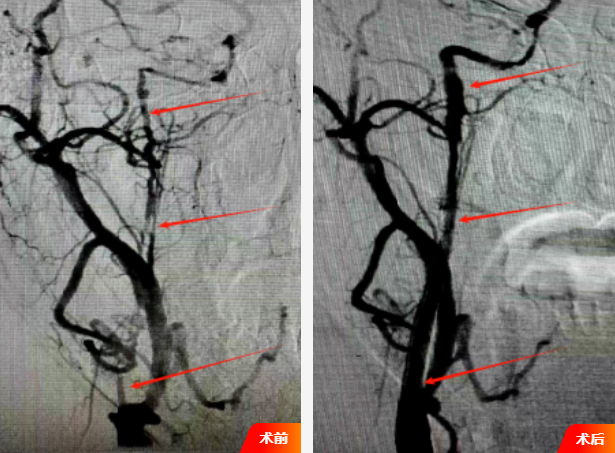

1、精准造影,锁定“元凶”:首先进行全脑血管造影(DSA),清晰显示右侧颈内动脉起始部至颅内段慢闭、重度狭窄,远端血流微弱,精准定位闭塞的部位,根据影像精准的测量出狭窄部位远端及近端血管的直径,并选择合适的支架。

2、小球囊开道:在微导丝的精确引导下,小心翼翼地穿越颈内动脉起始部至颅内段;随后,用小球囊由远及近逐步扩张,随着球囊充盈,造影显示,血流瞬间通过狭窄段,管腔恢复通畅。

3、支架精释,畅通无阻:一枚大小、长度经过精密计算的自膨式支架,在精确的影像引导下,支架被完美释放在预定位置,撑开满意;血流通畅。

4、血流奔腾,宣告胜利:最终造影结果令人振奋!颈内动脉血流完全恢复畅通,支架形态完美,位置满意,颅内远端血管显影清晰、充盈良好。